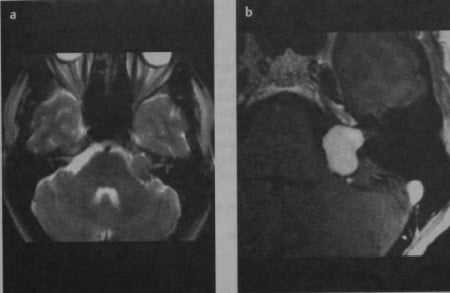

МРТ. шваннома преддверно-улиткового нерва у пациента с левосторонней потерей слуха. На Т2-взвешенном изображении (а) определяется опухоль мостомозжечкового угла, изоинтенсивная по отношению к ткани головного мозга. Мелкий узловой компонент опухоли в просвете слухового прохода более четко определяется на Т1-взвешенном изображении (b) с усилением после введения гадолиния.